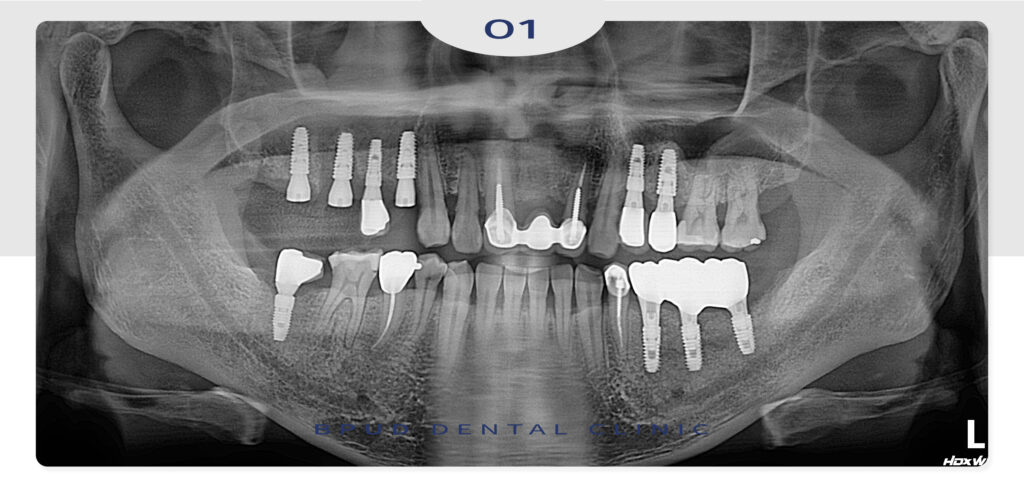

23.01.06

먼저 가장 심한 골 소실을 보이고 있었던

왼쪽 아래 임플란트와 크라운을 제거하였습니다.

이후 임플란트 식립을 진행하였는데요.

왼쪽 위,아래의 작은 어금니도 충치가 진행되고

골소실이 발경되어 발치 후 임플란트와

치조골 이식, 상악동 거상술을 시행하기로 하였습니다.